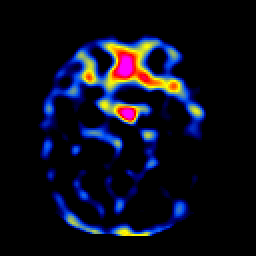

SPECT TL Study #1 -- Slice #19

[Home][Help][Clinical][Tour 1][Tour 2][Tour 3] Slice 19